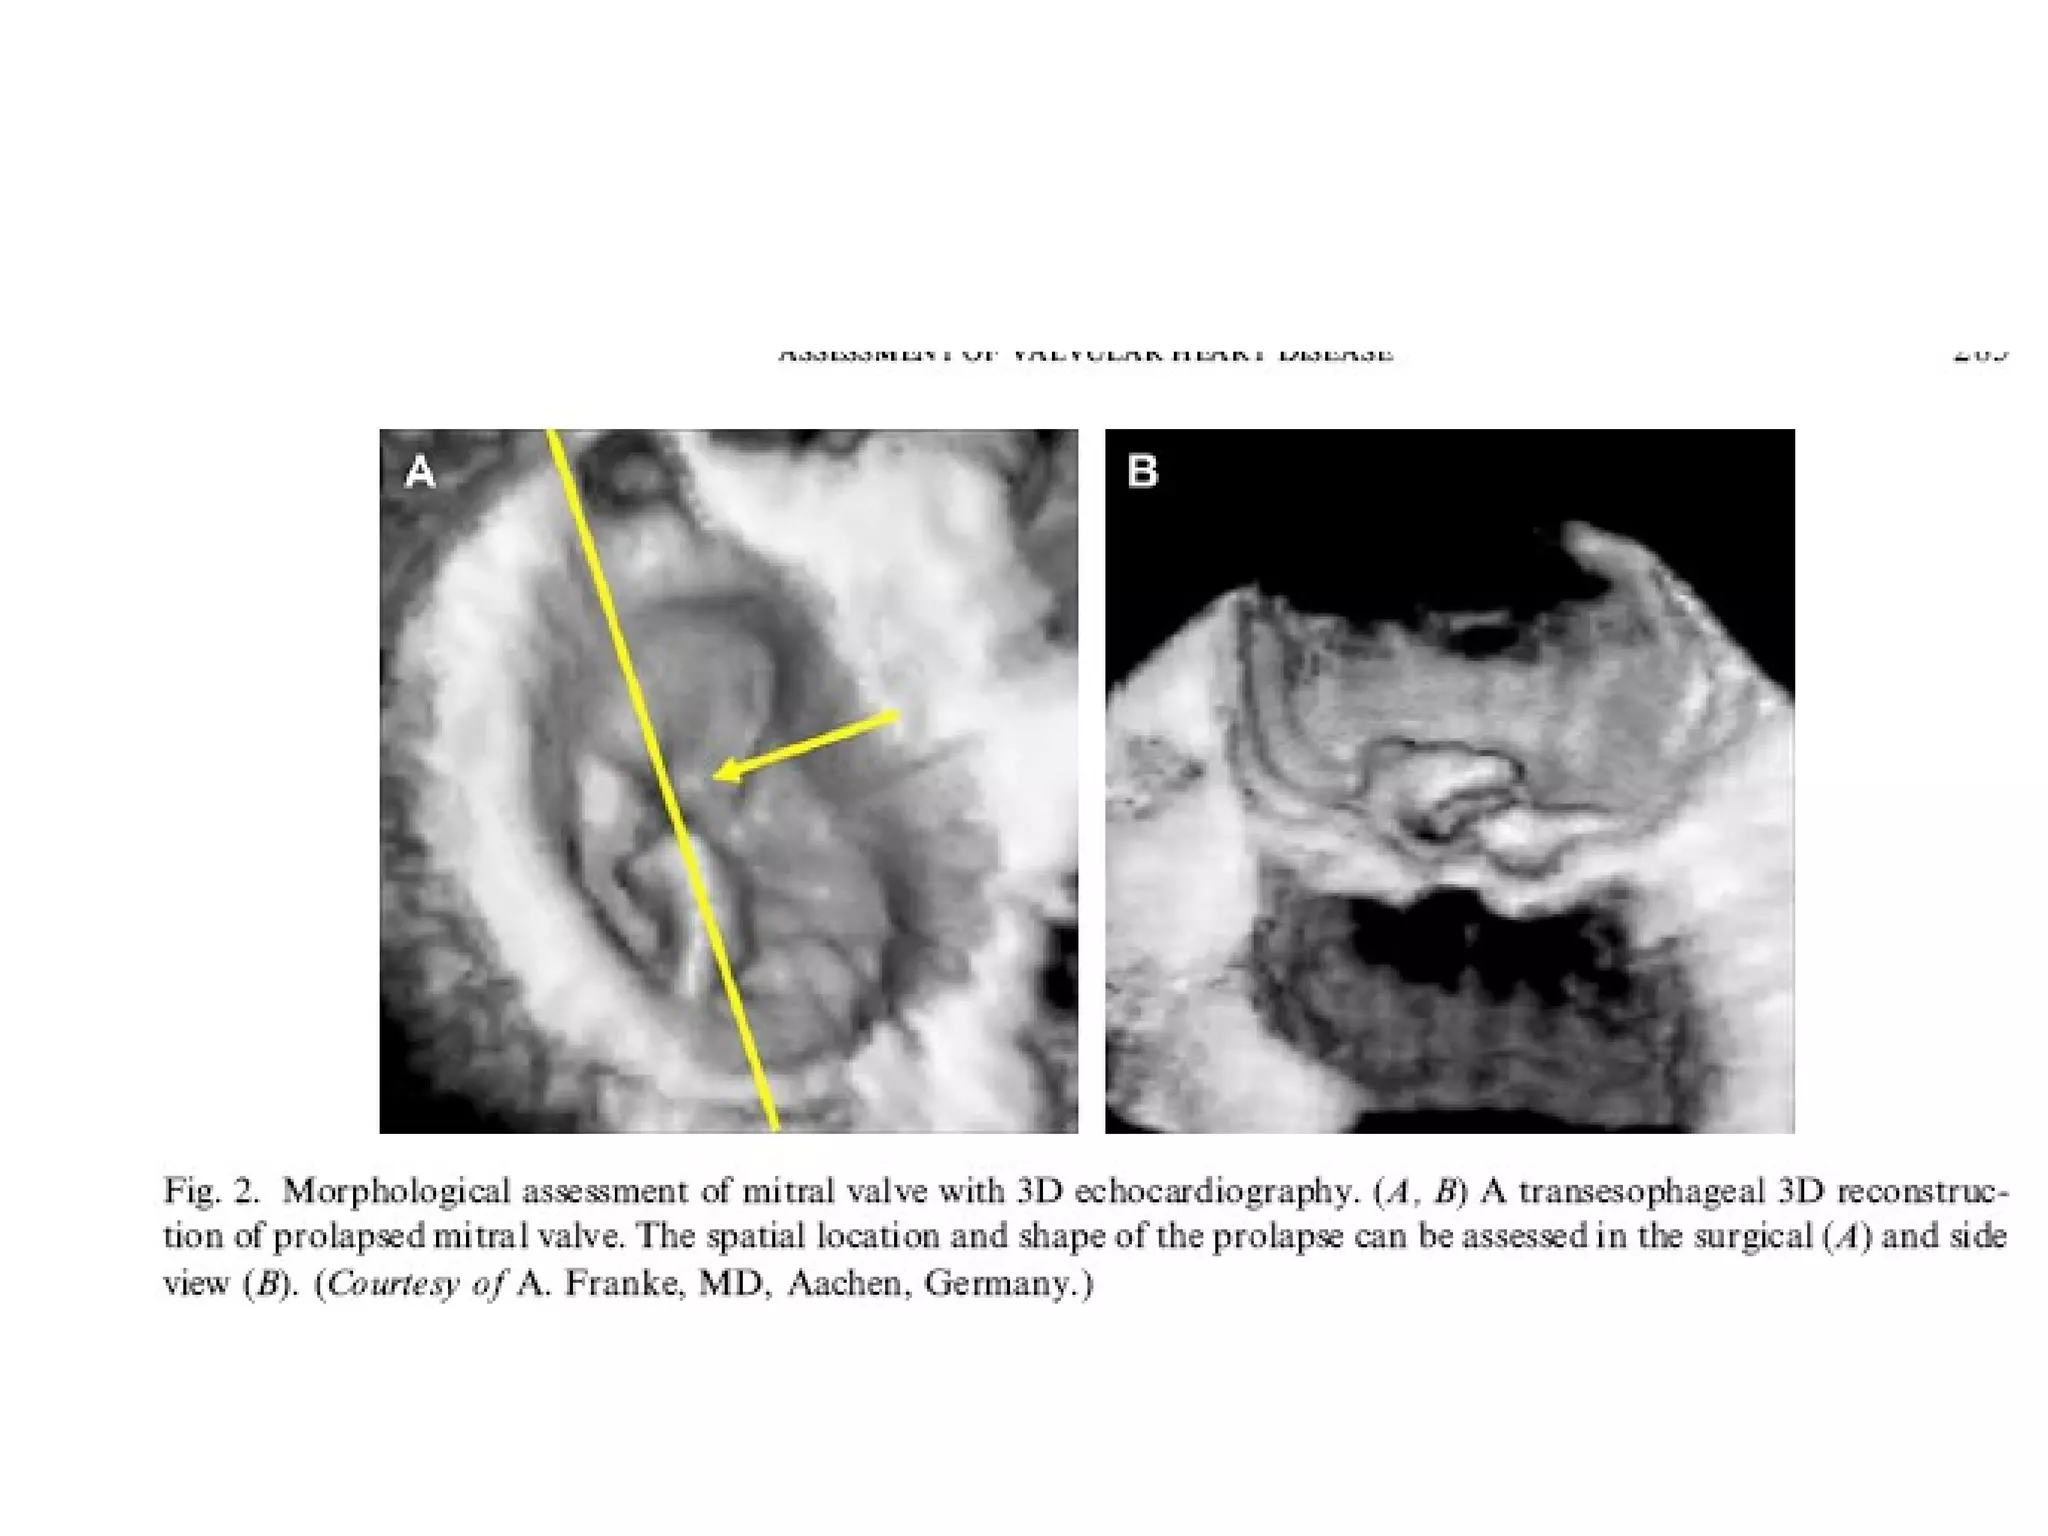

• Most studies have

been done on

mitral valve.

Understanding

about the mitral

valve annulus,

leaflet tethering,

tenting volumes

has improved with

the advent of 3 D

echocardiography